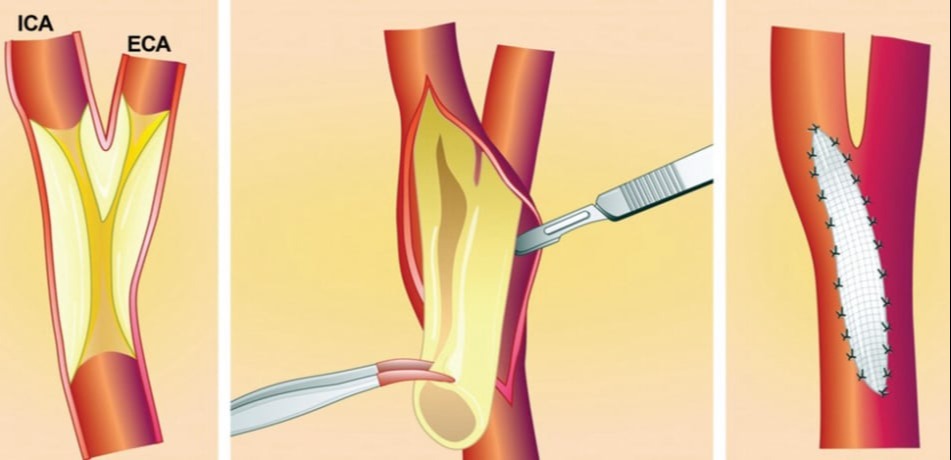

Η ενδαρτηρεκτομή καρωτίδας (carotid endarterectomy) είναι μια χειρουργική επέμβαση που χρησιμοποιείται για την αφαίρεση των αθηροματικών πλακών από την καρωτίδα αρτηρία. Ο σκοπός της επέμβασης είναι να αποκαταστήσει τη φυσιολογική ροή του αίματος προς τον εγκέφαλο και να μειώσει τον κίνδυνο εγκεφαλικού επεισοδίου (εγκεφαλικό επεισόδιο) που μπορεί να προκαλείται από τη στένωση της καρωτίδας.

Η ενδαρτηρεκτομή καρωτίδας (carotid endarterectomy) είναι μια χειρουργική επέμβαση που χρησιμοποιείται για την αφαίρεση των αθηροματικών πλακών από την καρωτίδα αρτηρία. Ο σκοπός της επέμβασης είναι να αποκαταστήσει τη φυσιολογική ροή του αίματος προς τον εγκέφαλο και να μειώσει τον κίνδυνο εγκεφαλικού επεισοδίου (εγκεφαλικό επεισόδιο) που μπορεί να προκαλείται από τη στένωση της καρωτίδας.